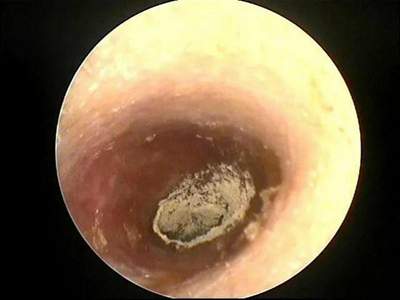

外耳道

脱屑

霉菌性外耳道炎外耳道有黄白色颗粒物图

霉菌性外耳道炎累及外耳道,皮损为大块黄白色的厚痂,同时伴随有鳞屑,边缘还有少许颗粒状脱皮,与周围皮肤界限清楚,周围明显红肿。